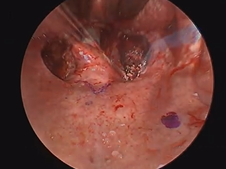

Transcervical Exploration of Parapharynx for Deep Lobe Parotid Pleomorphic Adenoma

Microdirect Laryngoscopy and CO2 Laser Total Vestibulectomy for Pyolaryngocele

Microdirect Laryngoscopy with CO2 Laser Wedge Excisions for Subglottic Stenosis